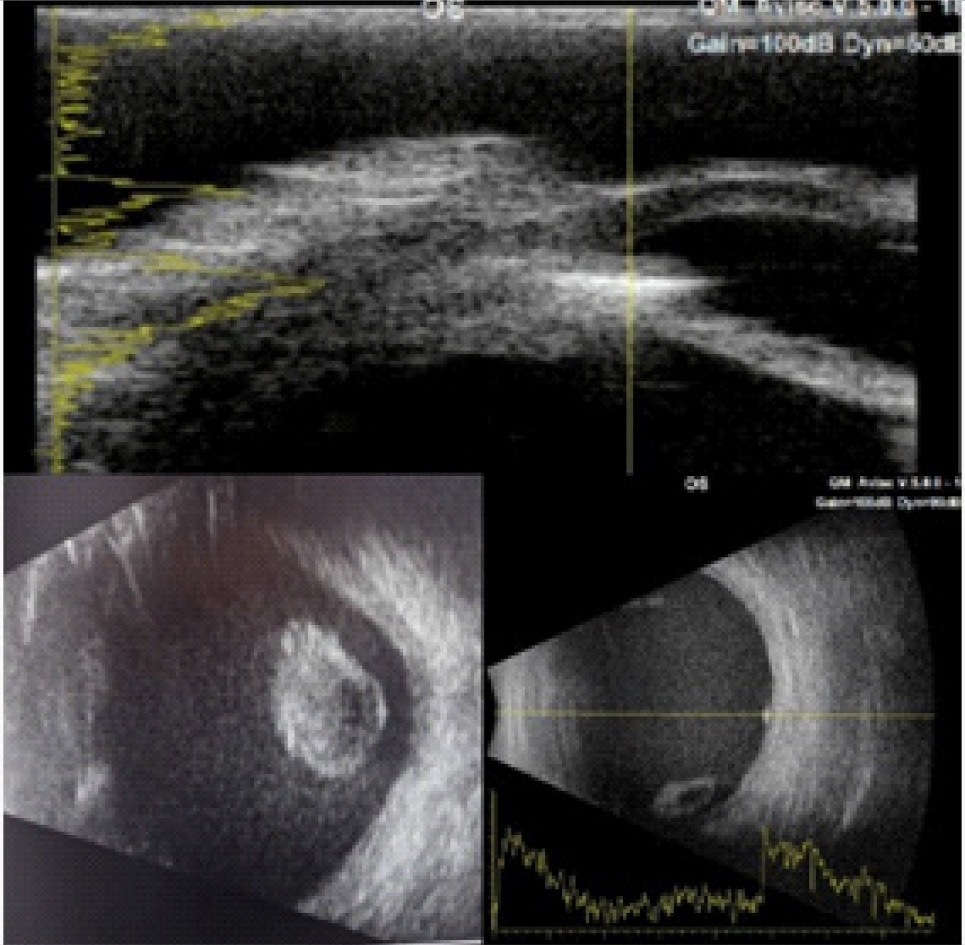

Пациенту был проведен комплекс инструментальных исследований, включающий в себя ультразвуковое исследование (УЗИ) и ультразвуковую биомикроскопию (УБМ), рентгенографию глазниц (РГ) с локализацией инородного тела по методу Комберга – Балтина, компьютерную томографию (КТ) головы. Эхографическая картина заднего сегмента OS имела следующие особенности: витреоретинальные тяжи, мелкодисперсная взвесь – выпот, хрусталик люксирован в стекловидное тело, нельзя исключить ВГИТ на глазном дне. УБМ выявила инородное тело в передней камере по меридиану 4–5 часов (рис. 2). При рентгенографии OS по Комбергу – Балтину определялось ВГИТ размерами 2 × 1 × 1 мм, по меридианам 4 часа 10 минут – 4 часа 40 минут, на расстоянии 4 мм от анатомической оси глаза, на расстоянии 1–2 мм от плоскости лимба (3–4 мм при пересчете на склеру) (рис. 3).

Рис. 2. УЗИ и УБМ левого глаза